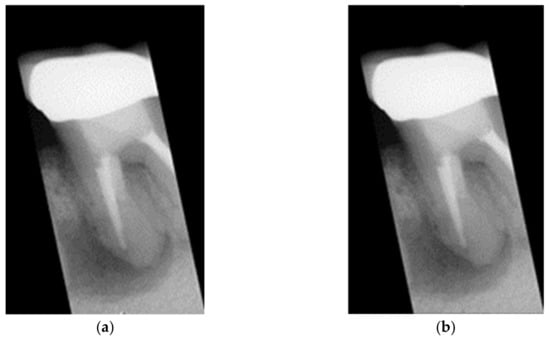

2.2. Enhancing Lesion

2.2.1. Grayscale Image

2.2.2. Gaussian High Pass Filter

2.2.3. Lesion Heightened